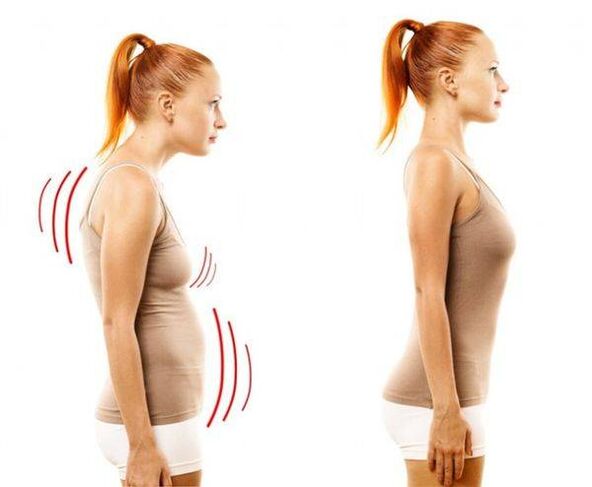

Ядро хрыбетнага дыска пры гэтай хваробе вытанчаецца і ўсыхае, фіброзная тканіна вакол яго пачынае разбурацца, храстковая тканіна падвяргаецца негатыўным зменам.Пазваночнік аказваецца няздольны спраўляцца са звычайнымі нагрузкамі - і выяўляецца гэта ў першую чаргу ў з'яўленні боляў, спачатку выяўленых невыразна, але з часам якія ўзмацняюцца ўсё больш.Аднак пры значных нагрузках - маларухомым ладзе жыцця, сядзячай працы, пастаянных стрэсах, дрэннай выправе і траўмах спіны - рана ці позна астэахандроз дзівіць грудны аддзел.Захворванне лічыцца вельмі распаўсюджаным - ад яго пакутуе кожны трэці дарослы чалавек.

Запушчаны астэахандроз хрыбетніка выяўляецца ў скаліёзе, часам хвароба пераходзіць на шыйныя пазванкі і становіцца прычынай страты голасу.